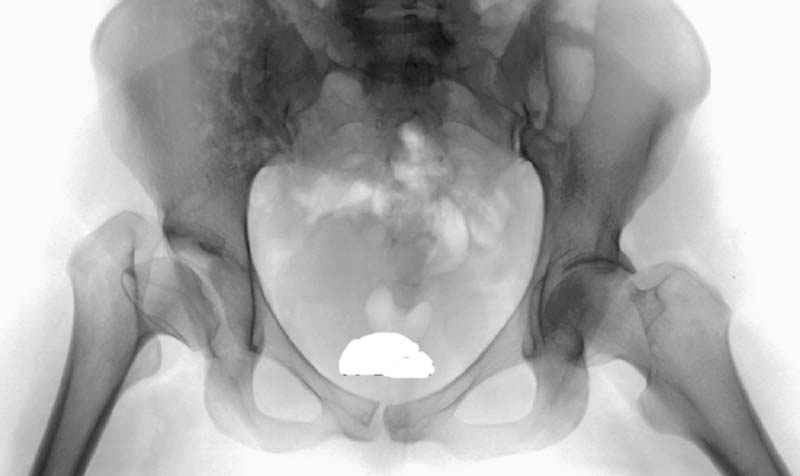

До настоящего времени считалось, что в одноопорном ортостатическом положении тазобедренный сустав функционирует как рычаг первого рода, таз удерживается в горизонтальном положении за счет отводящей группы мышц, а нагруженными являются верхние сектора головки бедренной кости и вертлужной впадины. Соответственно суммарная нагрузка на головку бедренной кости равна учетверенной массе тела (при условии, что плечо веса тела относится к плечу отводящих мышц как 1:3).Проведены экспериментальные исследования на трехмерной и плоскостной модели тазобедренного сустава, анализировались клинические, патоморфологические и интраоперационные наблюдения, изучен достаточный объем научных публикаций. Установлено, что в ортостатическом положении с опорой на одну ногу, а так же в средине одноопорного периода шага, тазобедренный сустав функционирует как рычаг второго рода. Это обеспечивается за счет натяжения связки головки бедра, которая ограничивает приведение бедра, наклон таза в неопорную сторону и разгружает отводящую группу мышц. Благодаря связке головки бедра происходит замыкание тазобедренного сустава во фронтальной плоскости, при этом основная нагрузка приходится на нижние сектора головки бедренной кости и вертлужной впадины. Согласно нашим приблизительным расчетам плечо силы реакции связки головки бедра относится к плечу веса тела как 1:3. Соответственно нагрузка на нижний сектор головки бедренной кости в одноопорном ортостатическом положении составляет в покое 2 веса тела. В качестве одного из наглядных доказательств можно привести иллюстрацию эксперимента на трехмерной модели тазобедренного сустава с аналогом связки головки бедра (Рис.1).

Соответственно результирующая сила (F3), воздействующая на нижний сектор головки бедренной кости составляет в покое удвоенный вес тела, если принять, что плечо силы реакции связки головки бедра относится к плечу веса тела как 1:3.: F3 = F2 - F1 Стремление натянутой связки головки бедра к вертикальности в одноопорном ортостатическом положении стабилизирует таз в горизонтальной и сагиттальной плоскости, а замыкание в сагиттальной плоскости обеспечивается натяжением подвздошно-бедренной связки. Все это создает предпосылки для высокой устойчивости одноопорного ортостатического положения. Кроме этого связка головки бедра еще обеспечивает разворот таза вперед в одноопорном периоде шага, определяет ритмичность ходьбы и снижает ее энергоемкость.Уточнение механики тазобедренного сустава позволяет пересмотреть взгляды на патогенез, симптоматику, диагностику, профилактику и лечение заболеваний тазобедренного сустава - коксартроз, асептический некроз головки бедра, врожденный вывих бедра (дисплазия), болезнь Пертеса, юношеский эпифизеолиз головки бедренной кости и ряд других патологических состояний. Кроме этого открываются пути для совершенствования конструкции эндопротеза тазобедренного сустава, разработки новых способов лечения травм и заболеваний тазобедренного сустава, прогнозирования их последствий. Как никогда актуальным становится вопрос о восстановлении связки головки бедра при ее повреждении или патологическом изменении.С уважением С.В.Архипов-БалтийскийE mail: postmaster@archipov.koenig.ru или archipovkgd@mail.ruПодробнее смотри:Авторский сайт: <Морфомеханика> www.enet.ru/~archipov/ (архив статей автора).Сайт <Градусник.ру>: www.gradusnik.ru/rus/doctor/morfomehanika/МонографияАрхипов-Балтийский С.В. Рассуждение о морфомеханике. Норма: В 2-х томах. - Калининград, 2004. - 820 с., ил. (Рукопись, версия 1.4, исправленная и дополненная, содержит 15 таблиц, 340 иллюстраций, библиография - 885 названий)Имеется в: Российской национальной библиотеке, г. Санкт-Петербург, Государственной центральной научной медицинской библиотеке, г. Москва<Ленинской библиотеке>, г. МоскваРоссийской книжной палате, г. МоскваМонография Архипов-Балтийский С.В. Ligamentum capitis femoris - ligamentum incognita. - Калининград, 2004. - 112 с.Имеется в означенных выше библиотеках, в библиотеках ряда НИИТО, некоторых университетов и мед.институтов.